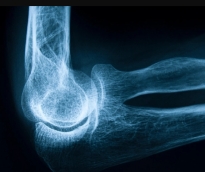

- تسجيل أكثر من 100 حالة لكسور مرتبطة بهشاشة العظام خلال 2023 أكدت مؤسسة حمد الطبية، أهمية توعية أفراد المجتمع بعوامل الخطورة المسببة للإصابة بهشاشة العظام ورفع مستوى الوعي حول أهمية صحة العظام، وتعزيز الكشف والتشخيص المبكر، والتعريف بالتدابير الوقائية للوقاية من هشاشة العظام.. وقد شاركت مؤسسة حمد الطبية في الاحتفال باليوم العالمي لهشاشة العظام تحت شعار»عظام قوية مدى الحياة» والذي يتم الاحتفال به بالتنسيق مع المؤسسة الدولية لهشاشة العظام لتعزيز صحة العظام والتشجيع على اتخاذ الإجراءات الوقائية للحفاظ على صحة العظام خلال جميع مراحل الحياة. من جانبه أشار الدكتور نبيل عبدالله، استشاري المفاصل وأمراض الروماتيزم بمؤسسة حمد الطبية إلى خطورة كسور الورك المرتبطة بهشاشة العظام، حيث تم تسجيل أكثر من 100 حالة في قسم الطوارئ بمستشفى حمد العام خلال عام 2023؛ قائلاً:» يمكن لكسور الورك أن تقلل من قدرة الشخص على التعايش بصورة مستقلة. وقال د. نبيل عبدالله:» أنشأت مؤسسة حمد الطبية عيادات متخصصة تهدف إلى الكشف المبكر عن الكسور المرتبطة بهشاشة العظام وعلاجها، حيث تعتبر عيادة خدمة تجبير الكسور الموجودة بمركز العظام والمفاصل ومستشفى الوكرة في طليعة هذه المبادرات. تركز هذه العيادة على تحديد المرضى الذين يعانون من الكسور جراء الإصابة بهشاشة العظام وضمان حصولهم على العلاج في الوقت المناسب لمنع وقوع مثل هذه الحوادث مستقبلاً. تهدف هذه العيادة من خلال البدء في العلاج مبكراً إلى الحد من مخاطر الإصابة بكسور إضافية بشكل كبير والتي قد تكون مؤلمة وتؤثر على جودة حياة الأفراد». وقال « بالإضافة إلى عيادة تجبير الكسور، تدير مؤسسة حمد الطبية عيادات أمراض الروماتيزم وهشاشة العظام، التي تقوم بفحص وعلاج المرضى المعرضين لخطر الإصابة بهشاشة العظام بصورة استباقية قبل تعرضهم للكسور. تأتي الإحالات إلى هذه العيادات غالباً من أطباء العظام والرعاية الأولية، تتوفر في الوقت الحالي مجموعة متعددة من خيارات علاج هشاشة العظام أكثر من أي وقت سابق إذ ثبت أن العلاجات تقلل من خطر الإصابة بكسور الورك بنسبة تصل إلى 40% وكسور العمود الفقري بنسبة 30 إلى 70%». واضاف أن هشاشة العظام تعتبر حالة تتسم بضعف وترقق العظام مما يزيد من خطر الإصابة بالكسور عند التعرض للحد الأدنى من الإصابات وخاصةً عند كبار السن. وشدد على أهمية الكشف المبكر والتوعية مشيراً إلى أن مرض هشاشة العظام يعرض الأفراد بشكل أكبر لخطر الإصابة بالكسور وخاصة عند كبار السن والنساء. وحول فعاليات الاحتفال باليوم العالمي لهشاشة العظام في مؤسسة حمد الطبية فقد ركزت على التثقيف حول التدابير الوقائية للحماية من الإصابة بهشاشة العظام.

مع التقدم في السن يخشى العديد من الناس إصابتهم بهشاشة العظام، ويشير الأطباء إلى أهمية الوقاية لتفادي الإصابة من هذه الحالة عبر التغذية السليمة. وتسبب هشاشة العظام ضعف العظام وترققها لدرجة أن أي سقوط أو مجهود بسيط مثل الانحناء أو السعال يمكن أن يسبّب كسورًا، وتحدث حالات الكسر المرتبطة بهشاشة العظام بصورة شائعة في الوِرك والرسغ والعمود الفقري، وفق مايو كلينك. وللحفاظ على صحة العظام والوقاية من هشاشتها فإن النظام الغذائي الغني بالكالسيوم يعد مثاليًا، بالإضافة إلى فيتامين د الذي يساعد الجسم على امتصاص الكالسيوم ثم إيداعه في العظام. وتحتاج العظام إلى العناصر الغذائية حتى تتمكن من النمو والحفاظ عليه، ويمكن أن يكون النظام الغذائي الصحي للعظام استراتيجية جيدة لمنع فقدان العظام المستمر، ويجب أن يكون النظام الغذائي جزءا من نمط حياة صحي شامل يتضمن التمارين ومستويات الكالسيوم وفيتامين د المثالية. وإليك خمس عادات من موقعميديكال إكسبرس لتناول الطعام جيدًا من أجل عظام قوية: 1- تناول الخضار والفواكه والحبوب الكاملة تناول المزيد من الخضار والفواكه ُيحسن صحة العظام، لأنها أطعمة منخفضة السعرات الحرارية والدهون بشكل عام، كما أنها غنية بالألياف والفيتامينات والمعادن الأساسية، وتحتوي على مواد كيميائية نباتية، وهي مواد يمكن أن تحمي من الأمراض المختلفة، بما في ذلك هشاشة العظام. وتحتوي الحبوب الكاملة على المزيد من العناصر الغذائية، وخاصة المغنيسيوم والألياف، مقارنة بالحبوب المكررة. 2- اختر مصادر صحية للبروتين والدهون يعد البروتين عنصرا مهما لصحة العظام لأنه مكون رئيسي في أنسجة العظام ويلعب دورا في الحفاظ على العظام، وأفضل الخيارات من البروتينات النباتية هي الفول والمكسرات، وكذلك الأسماك والدواجن منزوعة الجلد واللحوم الخالية من الدهون. وبحسب الدراسات يجب أن يمثل البروتين 25٪ إلى 35٪ من إجمالي السعرات الحرارية اليومية، والبروتينات النباتية غنية بالفيتامينات والمعادن والمركبات النباتية الشبيهة بالإستروجين التي تساعد في الحفاظ على العظام. وتعتبر منتجات الألبان قليلة الدسم، بما في ذلك الحليب والزبادي، مصدرا جيدا آخر للبروتين، وتوفر الكالسيوم الذي يفيد صحة العظام. 3- احصل على الكثير من الكالسيوم الكالسيوم ضروري لصحة العظام وهو لبنة أساسية في بناءها، ويساعد على منع فقدان العظام وكسور هشاشة العظام لدى كبار السن، على الرغم من أن المدخول اليومي الموصى به للبالغين يتراوح عمومًا من 1000 إلى 1200 ملليغرام، فإن النظام الغذائي النموذجي يوفر أقل من ذلك بكثير. منتجات الألبان التقليدية مثل الحليب واللبن والجبن، هي أغنى مصادر الغذاء، على سبيل المثال حصة واحدة من 8 أونصات من الحليب قليل الدسم أو كامل الدسم تحتوي على حوالي 300 ملليغرام من الكالسيوم. ومن المصادر الغذائية الغنية بالكالسيوم ما يلي: • مشتقات الحليب قليلة الدسم • الخضراوات الورقية ذات اللون الأخضر الداكن • السلمون المعلَّب مع العظام والسردين • منتجات الصويا مثل التوفو • حبوب الإفطار وعصير البرتقال المضاف إليهما كالسيوم 4 - الحد من السكر والملح والمضافات الفوسفاتية توفر الأطعمة التي تحتوي على السكريات المضافة أثناء المعالجة عموما الكثير من السعرات الحرارية والمواد المضافة والمواد الحافظة، لكنها تقدم القليل من الفوائد الصحية. ويعد الهدف من تقليل كمية الملح في النظام الغذائي لتسببه بـ زيادة كمية الكالسيوم التي يفرزها الجسم عند التبول. ويستخدم الفوسفور كمادة مضافة في العديد من الأطعمة المصنعة، يمكن أن يتداخل الكثير من الفوسفور في النظام الغذائي مع كمية الكالسيوم التي يتم امتصاصها من خلال الأمعاء الدقيقة. 5- التخفيف من استهلاك الكافيين يزيد الكافيين بشكل طفيف من فقدان الكالسيوم أثناء التبول، لكن الكثير من تأثيره الضار المحتمل ينبع من استبدال المشروبات التي تحتوي على الكافيين بالحليب والمشروبات الصحية الأخرى، ويعد الاستهلاك المعتدل للكافيين حوالي كوبين إلى ثلاثة أكواب من القهوة يوميا غير ضار طالما أن نظامك الغذائي يحتوي على الكالسيوم الكافي.